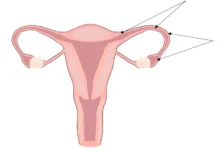

Популярная телеведущая одной из британских программ поделилась в эфире личным опытом, рассказав о последствиях операции по удалению яичников и маточных труб. Её откровенный рассказ вызвал широкий общественный резонанс.

Во время обсуждения эксперт ток-шоу отметила, что подобные процедуры значительно снижают вероятность развития онкологических заболеваний. «Это действительно устраняет риски! Теперь необходимо лишь поддерживать гормональный баланс с помощью минимальных доз специальных препаратов», — прокомментировала ведущая. Она также подчеркнула, что терапия проходит легко и не влияет на качество жизни.

Решение о проведении операции было принято после внезапного осложнения во время зарубежной поездки. Обследование выявило необходимость профилактического удаления кисты, что позволило избежать серьёзных последствий. После процедуры пациентка проходила реабилитацию дома, строго следуя рекомендациям врачей, и сейчас чувствует себя прекрасно.